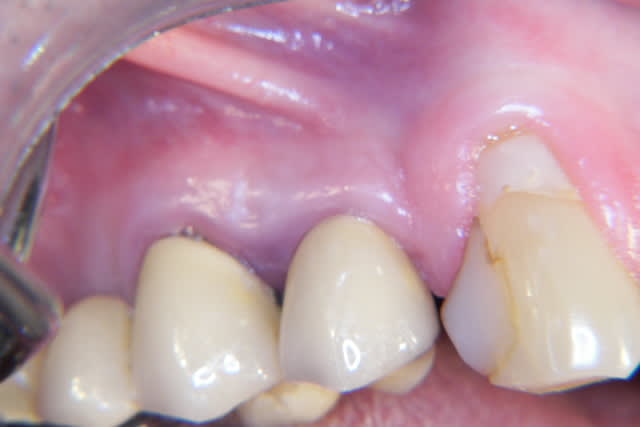

revu le patient hier... tissus mous totalement fibrosés suite à greffe ratée et retraction cicatricielle.

Je m'oriente donc avant sur récupération d'une gencive suffisament épaisse.

Greffe gingivale (conjonctif) pour avoir un bon tissu lors de la greffe osseuse,

Greffe osseuse (bloc autogène, menton)

Implants 21 et 22